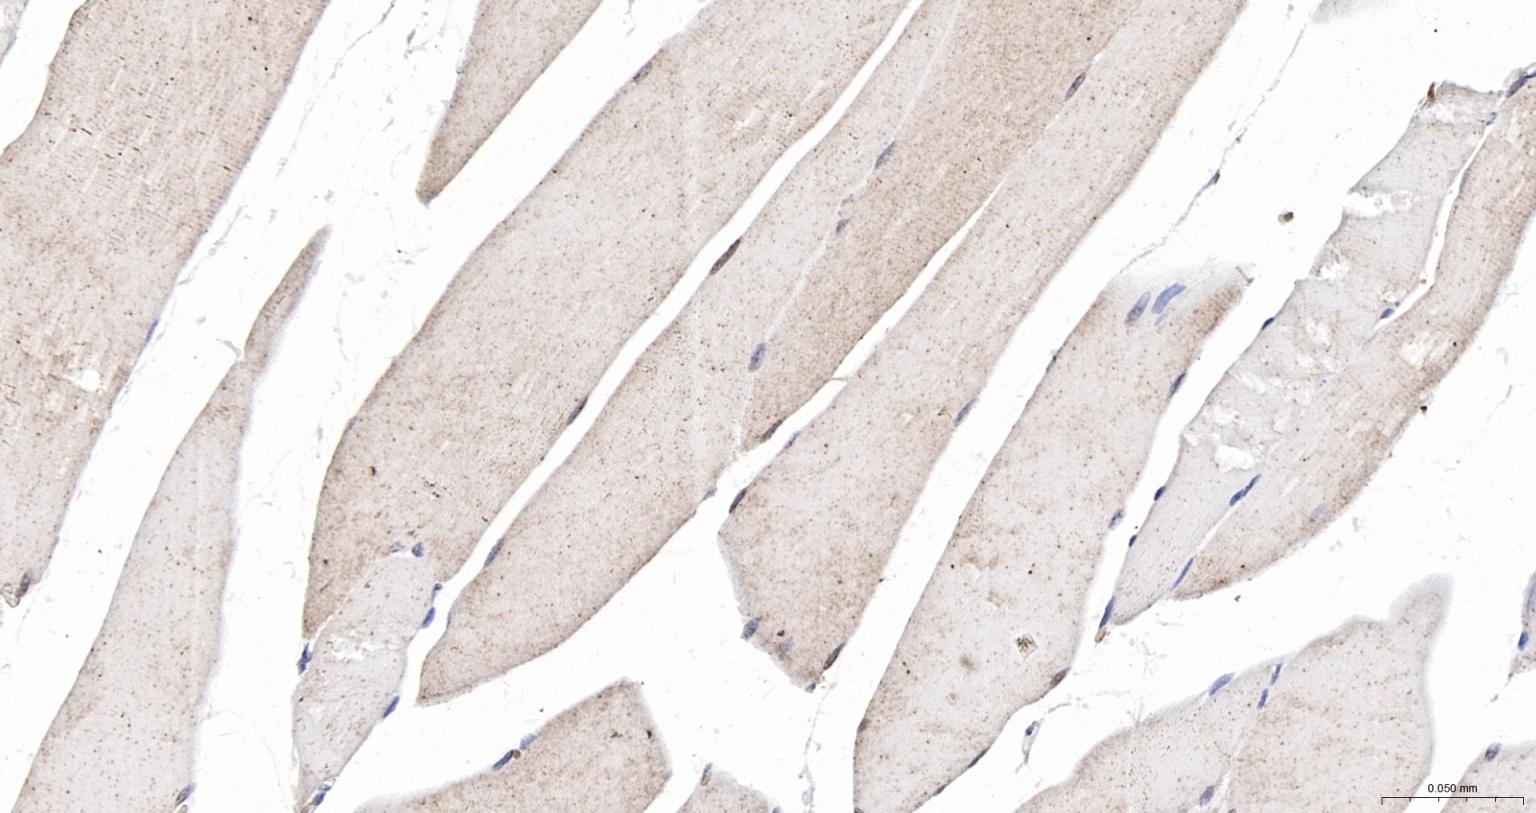

Paraformaldehyde-fixed, paraffin embedded Mouse Skeletal muscle; Antigen retrieval by boiling in sodium citrate buffer (pH6.0) for 15 min; The section was incubated with CSEN Polyclonal Antibody, Unconjugated (bs-9853R) at 1:200 overnight at 4°C, followed by conjugation to the bs-0295G-HRP and DAB (C-0010) staining.

Paraformaldehyde-fixed, paraffin embedded Rat Skeletal muscle; Antigen retrieval by boiling in sodium citrate buffer (pH6.0) for 15 min; The section was incubated with CSEN Polyclonal Antibody, Unconjugated (bs-9853R) at 1:200 overnight at 4°C, followed by conjugation to the bs-0295G-HRP and DAB (C-0010) staining.